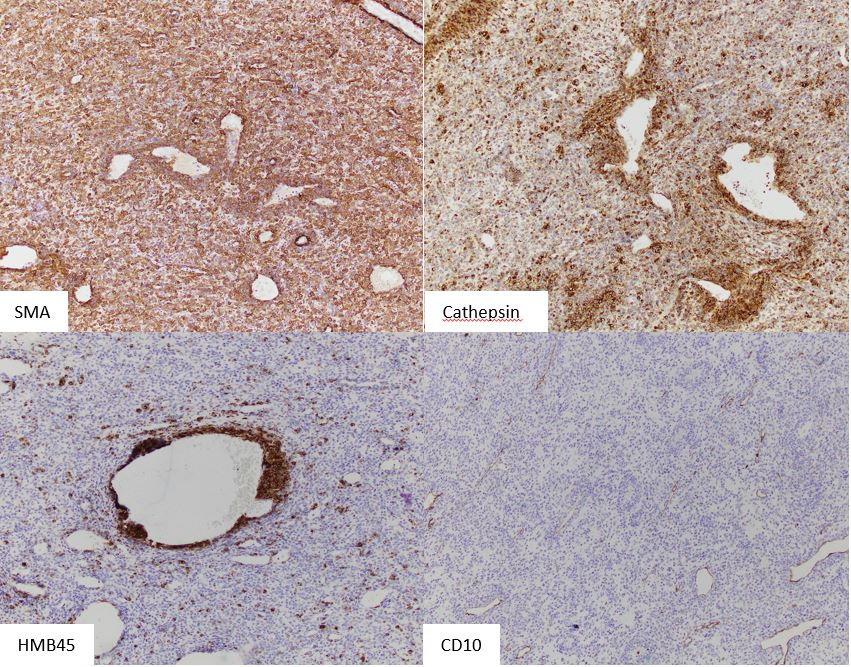

HMB45 is the most sensitive immunohistochemical marker, being expressed in up to 92% of cases. Melan-A and MITF are positive in a significant portion. About 80% stain for smooth muscle actin. A subset of cases show nuclear TFE3 expression. Genetically, PEComas may show inactivation of the TSC1 or TSC2 genes with subsequent activation of the mTOR pathway.